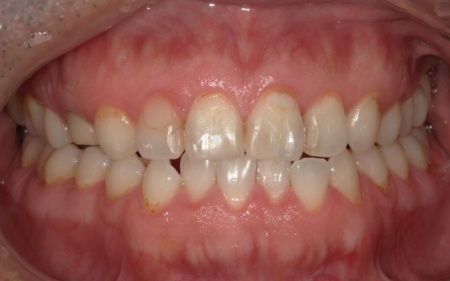

40代男性 長年放置していた虫歯や根尖性歯周炎などの口腔トラブルを全体的に治療した症例

「虫歯を長年放置してしまったので治療をしたい。また、見た目や噛み合わせの改善などを含めた、全体的な治療も行いたい」とご相談いただきました。

患者様は、10年ぶりに歯科医院を受診したとのことです。

レントゲン撮影をして詳しく検査したところ、複数の小さな虫歯が見られました。

また右上奥歯には、歯根の先に炎症が起きて膿が溜まる根尖性(こんせんせい)歯周炎が認められます。

さらに、左上奥歯(第1大臼歯)は温存が難しい状態でした。

以上のことから、口腔内を全体的に治療する必要があると診断しました。